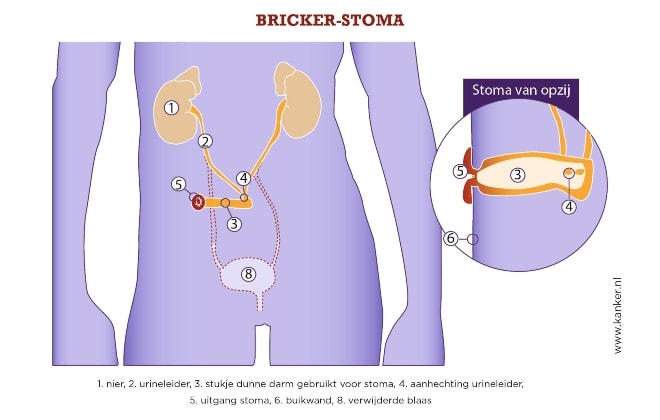

Brickerstoma

Het meest voorkomende type urinestoma is een uretero-ileo-cutaneostomie volgens Bricker, ofwel een Brickerstoma, waarbij de blaas in de meeste gevallen wordt verwijderd. Hiervoor gebruikt de uroloog een stukje ileum van 15-20 cm om een afvoer voor de urine te maken.

De 2 ureters worden aangesloten op deze ileumlis waarna het ene uiteinde van de lis wordt gesloten en het andere uiteinde als eindstandig stoma in de buikwand wordt gehecht, in principe rechtsonder op de buik.1-3 Tijdens de operatie plaatst de chirurg 2 slangetjes (splints) die via de ureters en de ileumlis uit het stoma komen. Zij zorgen ervoor dat de urine goed afvloeit en de aansluiting van de ureters op de ileumlis kan genezen. Meestal kunnen de splints na 7-10 dagen verwijderd worden.1

De ileumlis behoudt zijn samentrekkende beweging en omdat het stoma geen kringspier en reservoir heeft, loopt de urine vrijwel continu uit het stoma direct in het opvangzakje.1,3